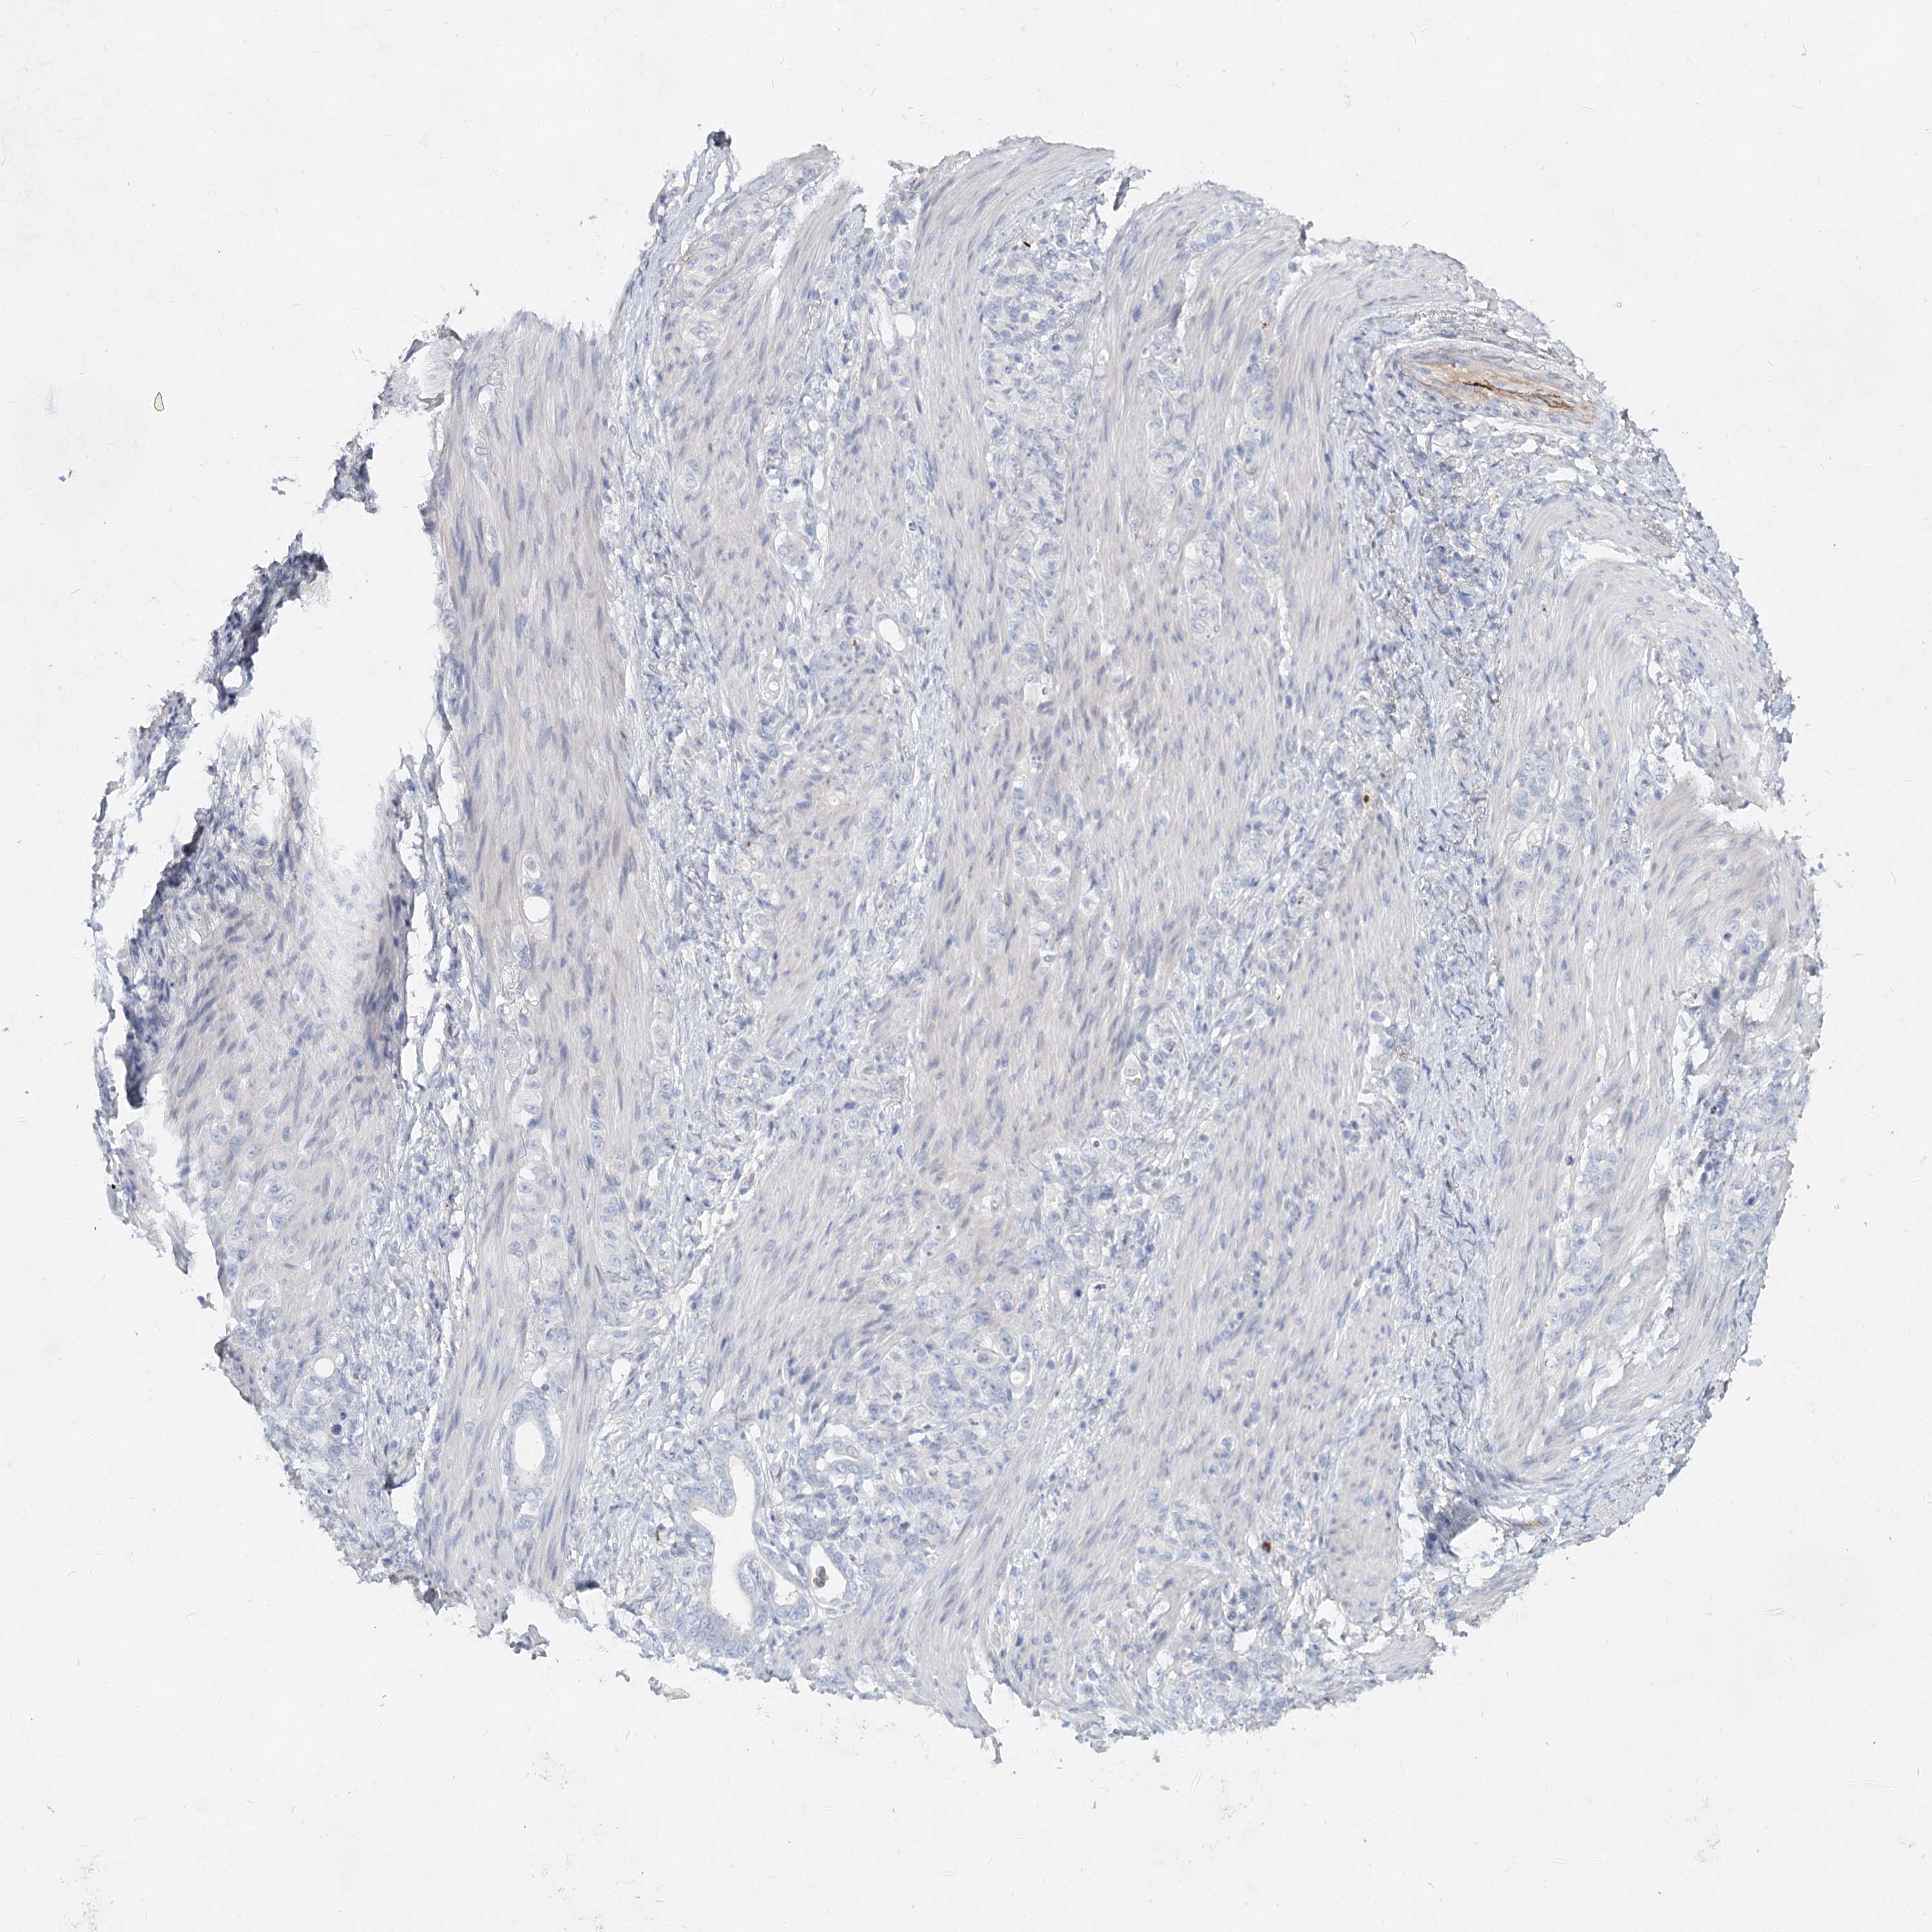

STOMACH CANCER - Protein expressioni

A mouse-over function shows sample information and annotation data. Click on an image to view it in a full screen mode. Samples can be filtered based on level of antibody staining by selecting one or several of the following categories: high, medium, low and not detected. The assay and annotation is described here.

Antibody stainingi

Antibody staining in the annotated cell types in the current human tissue is reported as not detected, low, medium, or high, based on conventional immunohistochemistry profiling in selected tissues. This score is based on the combination of the staining intensity and fraction of stained cells.

Each image is clickable and will lead to virtual microscopy that enables deeper exploration of all samples and also displays staining intensity scores, fraction scores and subcellular localization as well as patient and tissue information for each sample.

Antibody HPA038042

Antibody HPA038043

Staining

High

Medium

Low

Not detected

Intensity

Strong

Moderate

Weak

Negative

Quantity

>75%

75%-25%

<25%

None

Location

Nuclear

Cytoplasmic/membranous

Cytoplasmic/membranous,nuclear

Adenocarcinoma, NOS

Adenocarcinoma, High grade